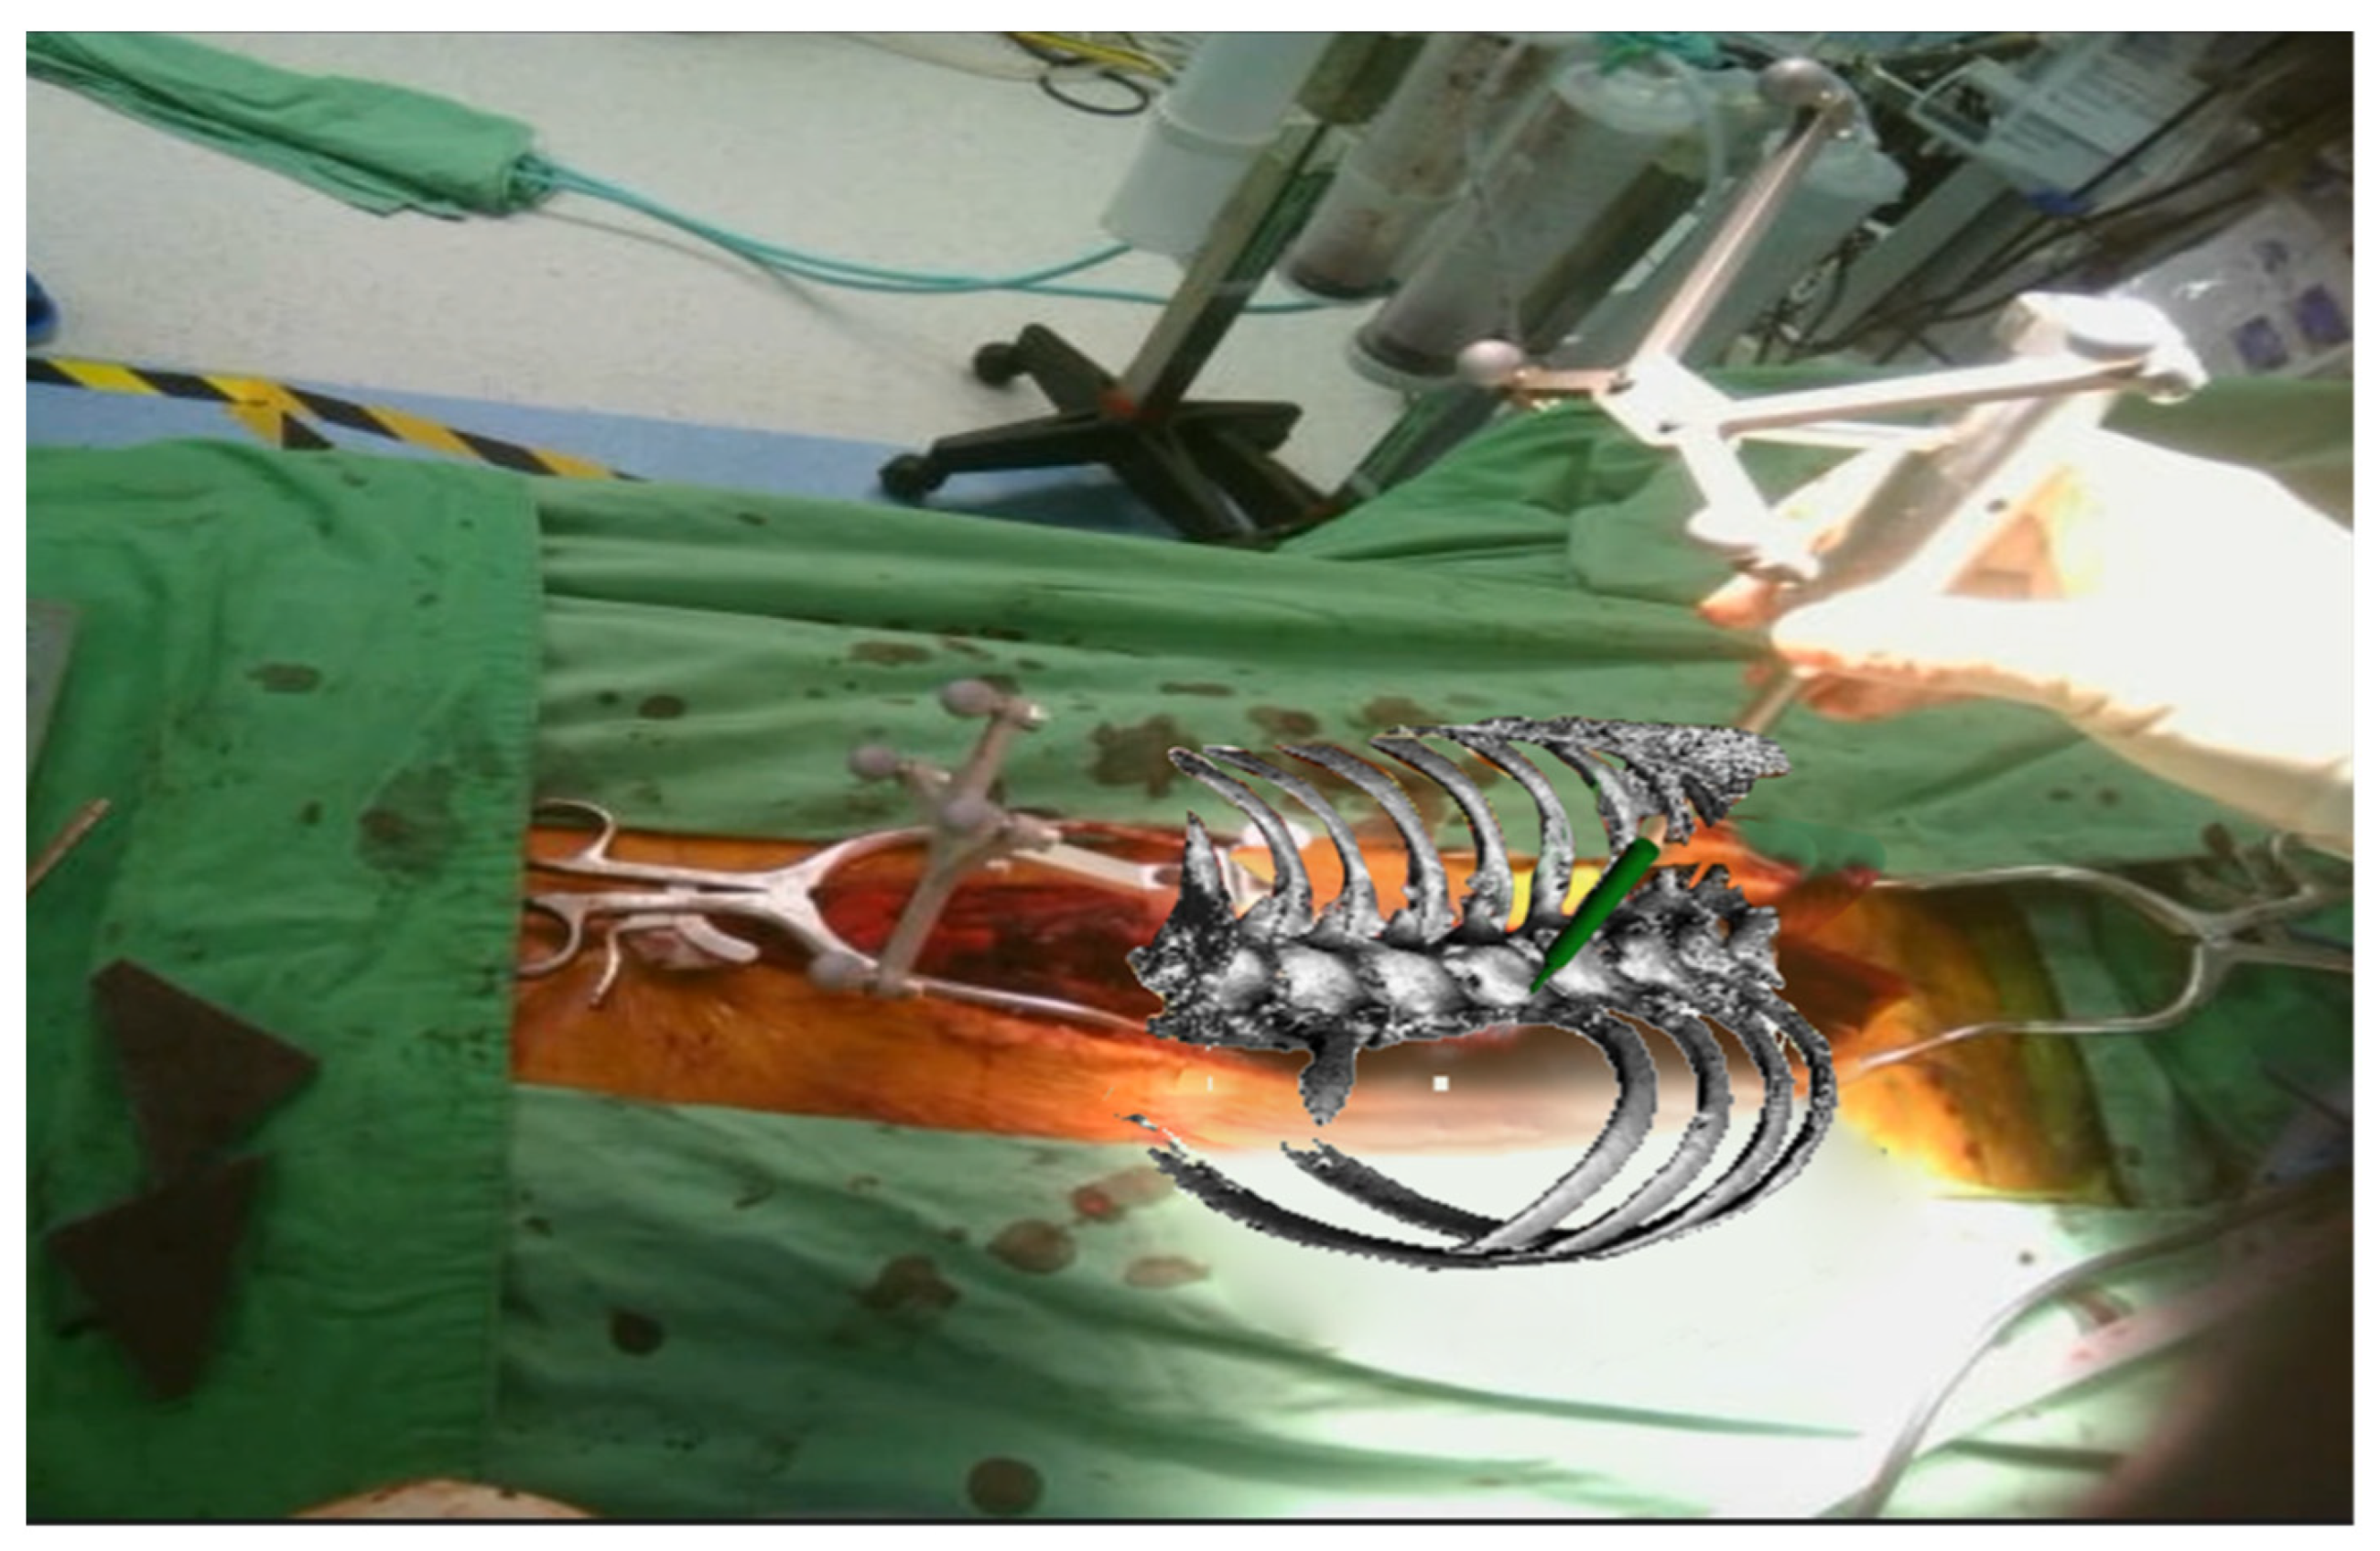

2.2. Registration Procedures

2.3. Surgical Techniques